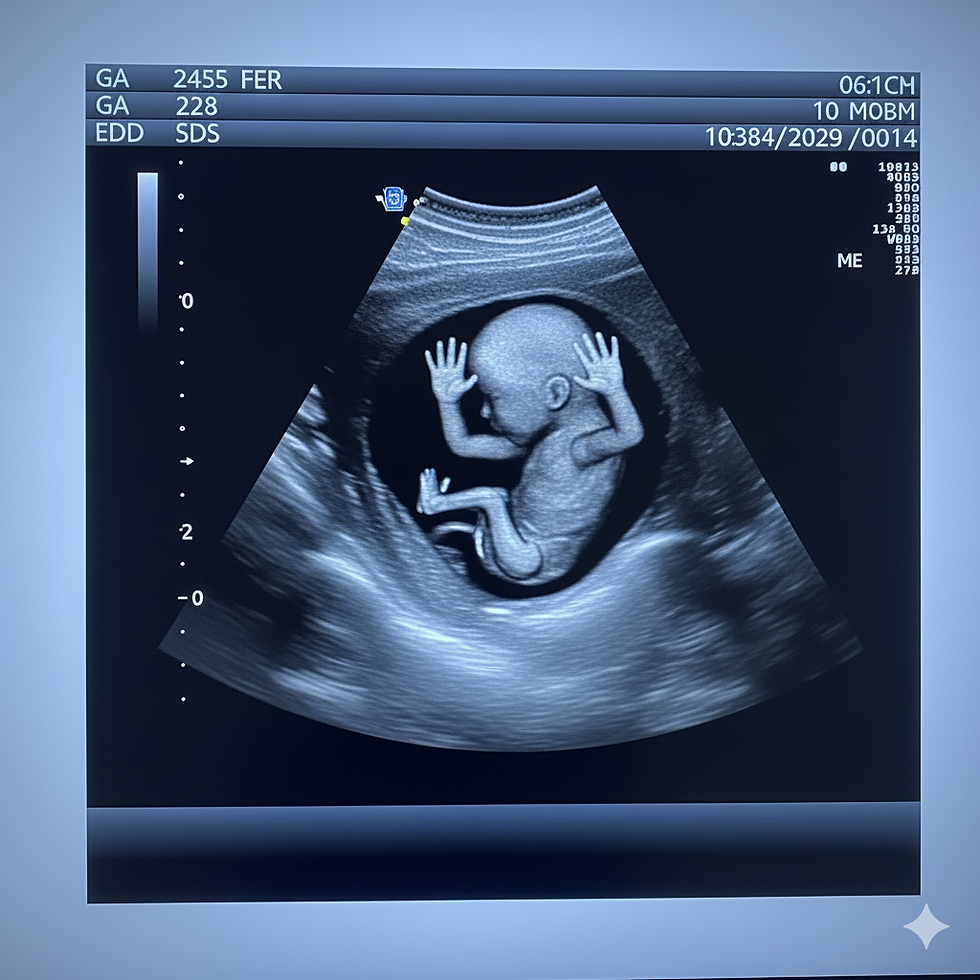

Do you need an ultrasound if you’re pregnant?

Around Vibrant Life Center lately, we are all talking babies and pregnancy. I can finally say without ruining any surprise, our wonderful Dr. Fleming is expecting. As such, we’ve got a plethora of “what about this?” and “what about that?” questions during pregnancies that have come up. The “Do I need an ultrasound?” question comes up for every mom.

If you’re the “crunchy” type and having babies at home with a lay midwife or doula, you may not need this information. But, just for exercise, let’s take a look at what the outcomes are for pregnancies with and without ultrasounds along the way. I’ll cut to the chase: There are no differences in outcomes. Here’s one version of that; Midwifery Today Prenatal Ultrasound Does Not Improve Perinatal Outcomes The heart and science of birth Even if you go to sites that ARE traditionally very pro medical procedures, they can’t point to any definitive benefit for uncomplicated pregnancies other than lowering the anxiety of the new mother and preparing the birth team for what may be a difficult delivery. What they DO identify and it's a big downside is about a 1 out of 11 chance the ultrasound will find something wrong that isn’t wrong at all. Once that happens, you’re up for the next procedure, replete with its OWN false positives and anxieties. False positive morphologic diagnoses at the anomaly scan: marginal or real problem, a population-based cohort study | BMC Pregnancy and Childbirth | Full Text This paper’s conclusion is doing these may cause further testing and MORE anxiety for the new mother.

This doesn’t render the technology bad. It’s a great tool for diagnosing and solving problems. Pregnancies for moms in their 40s DO have more complications. There are a handful of other reasons to employ this technology. Routine, uncomplicated pregnancy isn’t one of them.